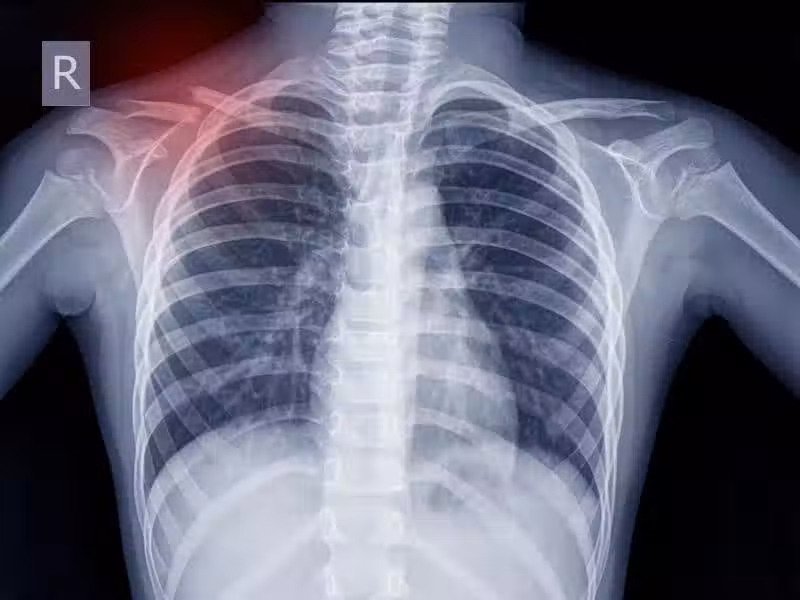

肺癌開始時!四肢可能會有「3個跡象」 醫生勸:哪怕「有了1個」都應該重視

其實和多數癌症一樣,肺癌在早期階段,症狀也不明顯、不典型。

很容易和其他呼吸系統疾病相混淆,等到症狀嚴重或者自行用藥無效來醫院檢查時,往往都已經發展至中晚期。

當然,肺癌開始時,並非一點信號都沒有,只是患者容易忽視。 如果四肢有3個跡象,哪怕僅有1個,也應該給予重視!